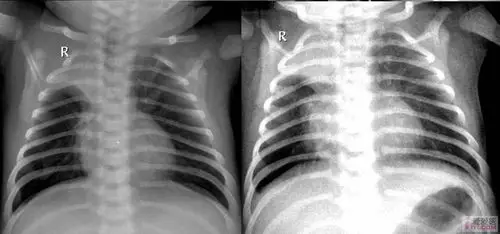

【讨论】两例患儿的胸片

图片尺寸1164x545

小儿呼吸道合胞病毒肺炎

图片尺寸500x338